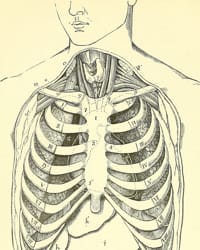

A cervical rib is an extra rib in the lower neck, above the normal first rib. Overall, cervical ribs are seen in about 0.5 to 1% of the human population. In detail, a cervical rib may be unilateral or bilateral, small or large, free-floating or fused to the first rib on the same side. While many physicians associate cervical ribs with thoracic outlet syndrome, the presence of a cervical rib does not prove or disprove thoracic outlet syndrome. Demonstration of cervical ribs goes back centuries, but association with TOS was only demonstrated in the early 19th century.

Sir Astley Cooper was one of the leading surgeons of his day, publishing seminal work on the repair of inguinal hernias, and becoming renowned as a vascular surgeon. He was named sergeant surgeon to Kings George IV and William IV, and to Queen Victoria, and founded the famous medical school at Guy’s Hospital in London Even though the cervical rib had been known for centuries, its effect on nearby structures was not documented until 1818, when Cooper described a young woman with pulselessness and gangrenous spots on her fingers, in conjunction with a palpable hard mass at the base of the neck. Cooper described, “I have however seen an exostosis arise from the sixth or seventh cervical vertebra, or perhaps from both” when introducing this case. Cooper attributed the patient’s symptoms to “a projection of the lower cervical vertebra towards the clavicle, and consequent pressure upon the subclavian artery.” Whether he in fact described a cervical rib or a C7 exostosis is unclear, but is a moot point. He had certainly presented the first description of arterial TOS. Thus began the era of the Cervical Rib Syndrome.

Holmes Coote performed the first TOS surgery. A 26 year-old female servant described a hard mass in her left lower neck, present since childhood. The “tumor” had grown recently, and she experienced paresthesias in the tips of her fingers, with loss of pulses at the wrist, wasting of muscles in the arm, and weakness leading to dropping of items. Mr. Coote explored the area while the patient was “fully under the influence of chloroform.” He noted a bony ‘tumor,’ which he had to divide from the cervical vertebra. He also found it was attached to the first rib anteriorly. He removed as much of the ‘tumor’ as he could, and pulses returned in the left upper extremity. Coote described his trepidation at exploring this area thusly: “But the region was not a pleasant one for any proceeding demanding the use of the knife. The subclavian artery and vein were in front; the axillary plexus of nerves lay spread out above; below, the apex of the lung, covered by the pleura, rose up in dangerous proximity; on the scalenus was the phrenic nerve; while towards the mesial line were the important vessels and nerves passing to the head, together with the vertebral vessels and thoracic duct. You can understand, therefore, why I was cautious in what I did.” The bony tumor was referred to as “an exostotic growth from the transverse process of the seventh cervical vertebra,” and “a development of the costal element, the rib, of the seventh cervical vertebra.” Thus, Coote became the first person to surgically treat a TOS patient.